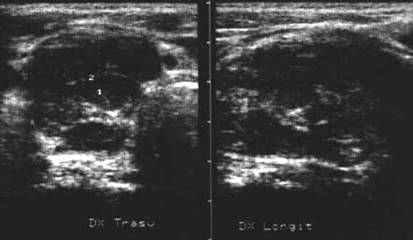

Adenom CU celule Hurthle

Femeie 76 ani. Formatiune nodulara mare in regiunea medio-apicala a lobului drept, de 26 x 37 x 42mm (20 cc), cu margini nu foarte bine definite. La exsamenul citologic prin citoaspiratie: lesiune foliculara (membrana pluristratificata de celulele lui Hurthle cu anizonucleoza).

Aceeasi pacienta. Vascularizatie bogata peri si intranodulara.

Lob drept , proiectie longitudinala si trasversala .

Barbat de 44 ani. Nodul mare in lobul drept si istm de 31x44x44mm, (30 cc) cu contur net, hipoecogen, neomogen, cu macrocalcificare.

Examn citologic: neoplazie oncocitara (a c. Hurthle).

Examen histologic postoperator: adenom cu celule Hurthle.